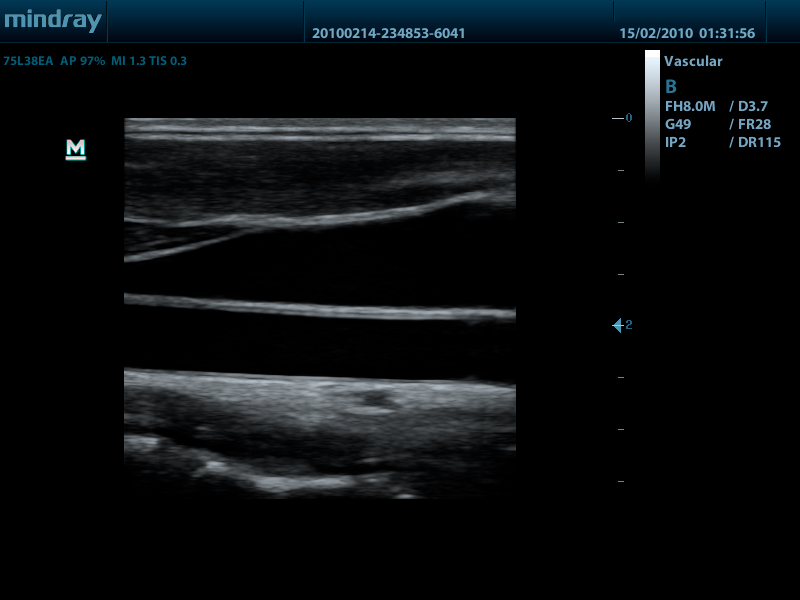

Линейный датчик 75L38EA (5.0/7.5/8.5/10.0/Н8.0/Н10.0 МГц, 38 мм)

Линейный датчик 75L53EA (5.0/7.5/8.5/10.0/Н8.0/Н10.0 МГц, 50 мм)